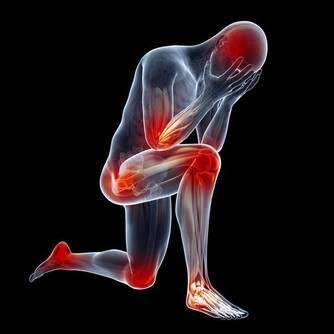

9. 狼瘡狼瘡是一種自身免疫性疾病,影響身體的許多系統和器官,皮膚也包含在內。該病的早期症狀之一,是在臉頰和鼻樑處出現蝴蝶形狀的紅棕色皮疹。當病情爆發時,皮疹看起來像是臉被曬傷了,這種皮疹的醫學術語是顴骨皮疹。狼瘡是一種需要看醫生的病症,它無法治愈,但治療可以幫助減少發作次數以及減少並發症。